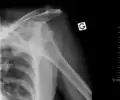

Anterior dislocation of the left shoulder.